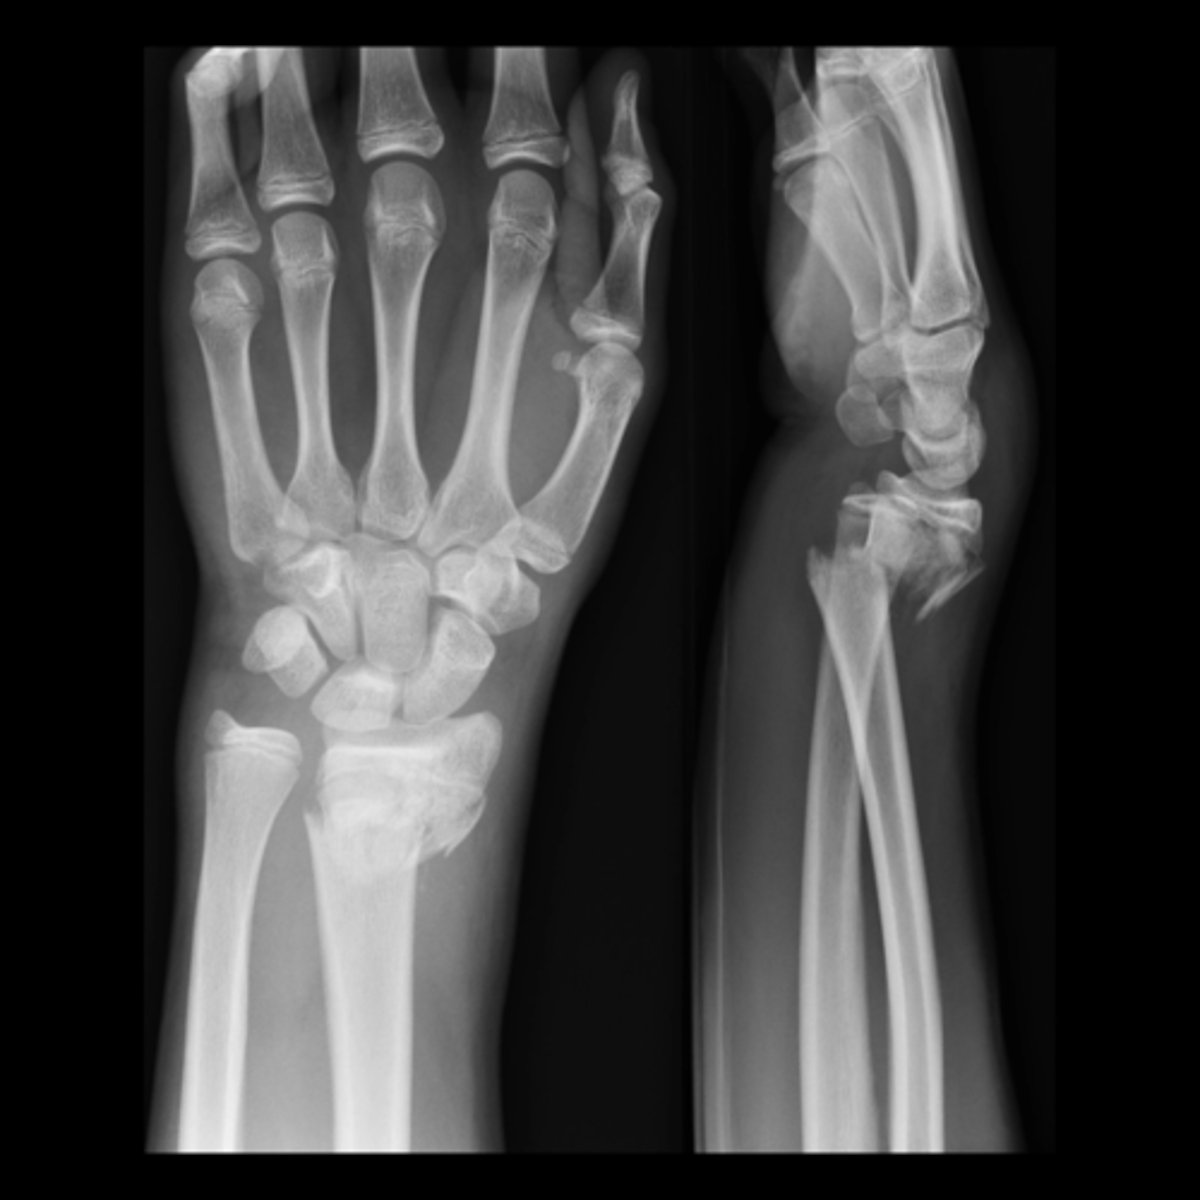

what is this

fall on outstretched hand

FOOSH

describe

no fracture

FOOSH, distal radial fracture

distal radial fracture

distal portion of the distal bone pointing towards the dorsum (back) of the hand

Colles Fractures

colles fracture